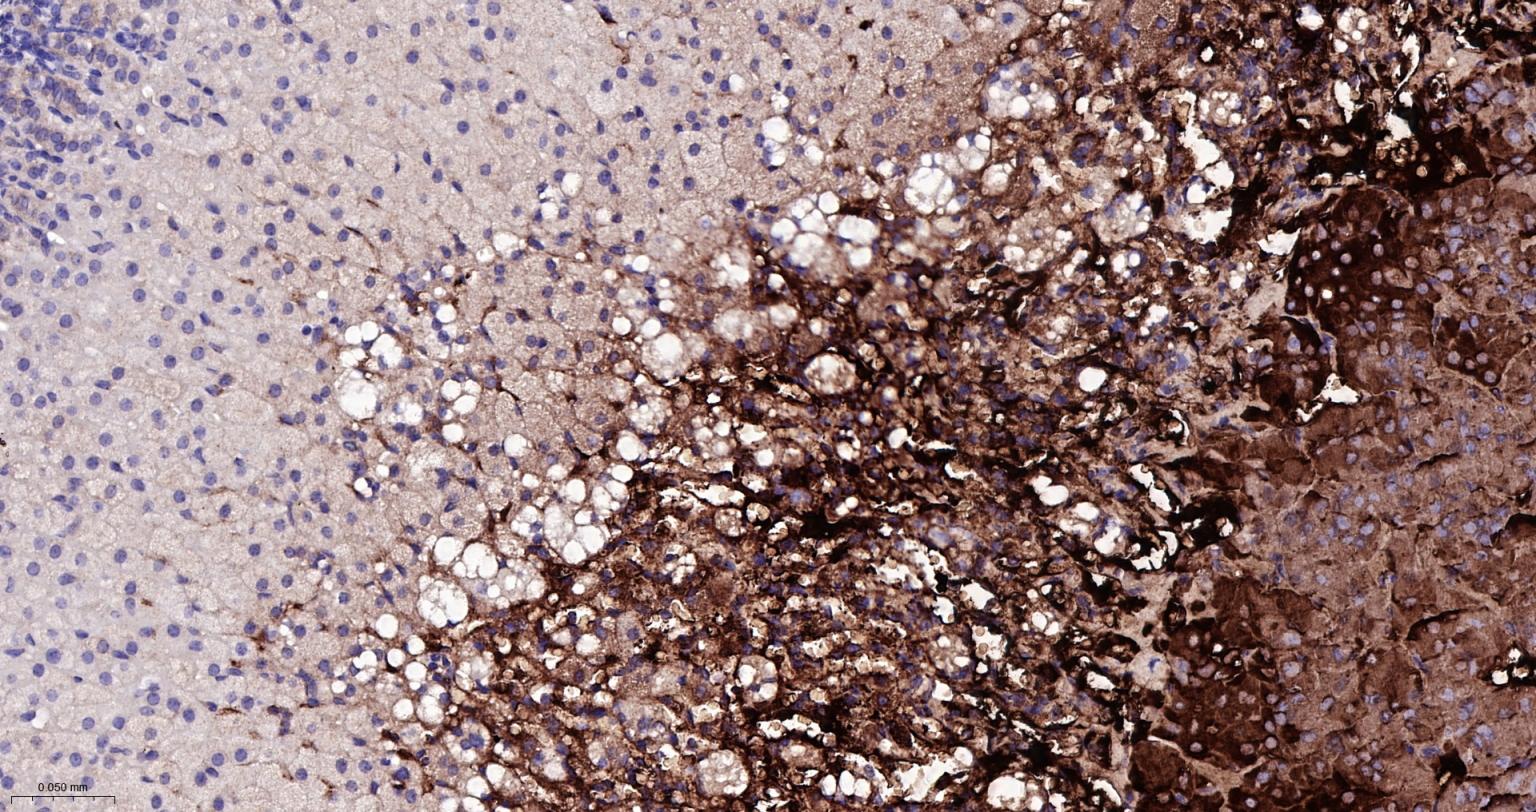

Paraformaldehyde-fixed, paraffin embedded Human Adrenal Gland; Antigen retrieval by boiling in sodium citrate buffer (pH6.0) for 15 min; Antibody incubation with Tyrosine Hydroxylase Monoclonal Antibody, Unconjugated(bsm-52574R) at 1:200 overnight at 4°C, followed by conjugation to the bs-0295G-HRP and DAB (C-0010) staining.

Paraformaldehyde-fixed, paraffin embedded Mouse Adrenal Gland; Antigen retrieval by boiling in sodium citrate buffer (pH6.0) for 15 min; Antibody incubation with Tyrosine Hydroxylase Monoclonal Antibody, Unconjugated(bsm-52574R) at 1:200 overnight at 4°C, followed by conjugation to the bs-0295G-HRP and DAB (C-0010) staining.